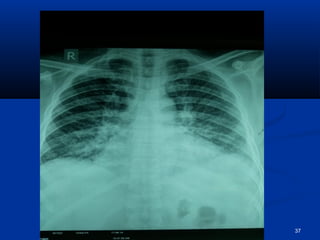

CCXXRR--PPAA

37

CCXXRR-PPAA .. FFiinnddiinnggss ooff ppuullmmoonnaarryy eeddeemmaa rreessoollvveedd 54

pprrooggrreessss  HHeeiiss aaffeebbrriillee && AAccttiivvee  SShhoorrttnneessss ooff bbrreeaatthh sseettttlleedd  RRtt.. SSiiddeedd WWeeaakknneessss iimmpprroovviinngg  LLeefftt ppoosstt.. ttiibbiiaall aarrtteerryy ggoott jjuusstt ppaallppaabbllee.. DDoorrssaalliiss ppeeddiissuuss nnoott ppaallppaabbllee yyeett.. ppaaiinn iinn lleegg iimmpprroovveedd.. lleevveell ooff ccoollddnneessss iinn lleefftt lleegg ddeeccrreeaasseedd ttoo lloowweerr 11//33rrdd RRFFTT’’ss ggoott bbaacckk ttoo nnoorrmmaall.. CCXXRR-PPAA .. FFiinnddiinnggss ooff ppuullmmoonnaarryy eeddeemmaa rreessoollvveedd 54